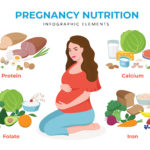

5 Key Nutrients for a Healthy Pregnancy Diet and Their Benefits

Author –Dr Preety Aggarwal MBBS, DGO, DNB, Medical Director (Gurgaon)- Obstetrics and Gynaecology 5 Key Nutrients for a Healthy Pregnancy Diet and Their Benefits Introduction During pregnancy, the mother must provide nutrition to herself and the baby. Hence, the nutritional requirements are higher during pregnancy. Out of which, certain vitamins are crucial for the overall […]

5 Key Nutrients Every Pregnant Woman Should Prioritize

Author –Dr Preety Aggarwal MBBS, DGO, DNB, Medical Director (Gurgaon)- Obstetrics and Gynaecology 5 Key Nutrients Every Pregnant Woman Should Prioritize Introduction: A balanced diet is of utmost importance when you are pregnant. As the adage goes, “You are what you eat”, Eating the right nutrients for your baby is essential for overall growth and […]